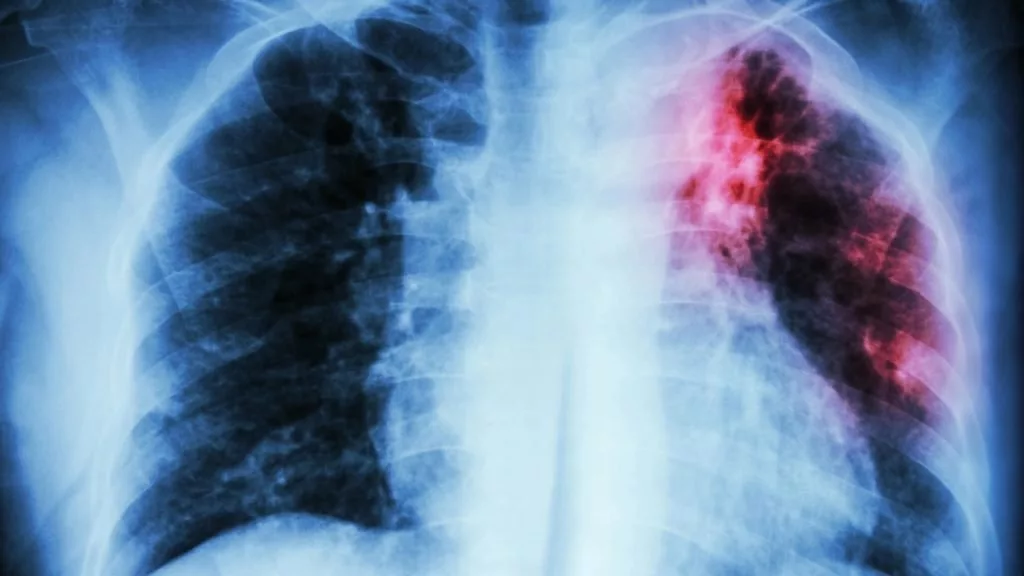

دیجیاتو: سازمان بهداشت جهانی (WHO) اعلام کرد که بیماری سل (Tuberculosis) همچنان جایگاه مرگبار خود بهعنوان کشندهترین بیماری عفونی جهان را حفظ کرده و در سال ۲۰۲۴ جان ۱.۲۳ میلیون نفر را گرفته است.

براساس گزارش جهانی سل ۲۰۲۵، این بیماری عفونی در سال گذشته میلادی کشندهترین بیماری عفونی بوده است. البته جهان برای اولینبار پس از همهگیری کووید-۱۹، شاهد کاهش همزمان موارد ابتلا به سل (نزدیک به ۲ درصد) و مرگومیر ناشی از آن (۳ درصد) بوده است. اما WHO هشدار میدهد که این دستاوردها شکننده هستند.